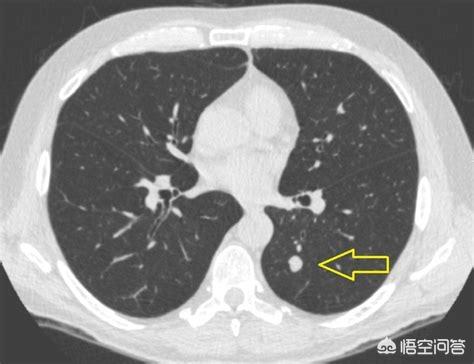

Der Pfeil zeigt auf den Knoten, der sehr klein war, als er im März 2016 entdeckt wurde, etwa 0,5 cm, und jetzt werden bei Routineuntersuchungen sehr viele Knoten wie dieser entdeckt.Es gibt keine Möglichkeit, auf den Bildern festzustellen, ob es gut- oder bösartig ist, sondern nur die Möglichkeit der Überprüfung, und die Überprüfung und Nachsorge ist auch das beste Mittel.

Sieben Monate später, bei der zweiten Nachuntersuchung im Oktober 2016, wurde deutlich, dass dieser Knoten größer und runder geworden war. Der vergrößerte Knoten bei der Nachuntersuchung sollte auf die Möglichkeit einer Bösartigkeit hinweisen, aber dieser Patient entschied sich dennoch nicht für eine Operation.